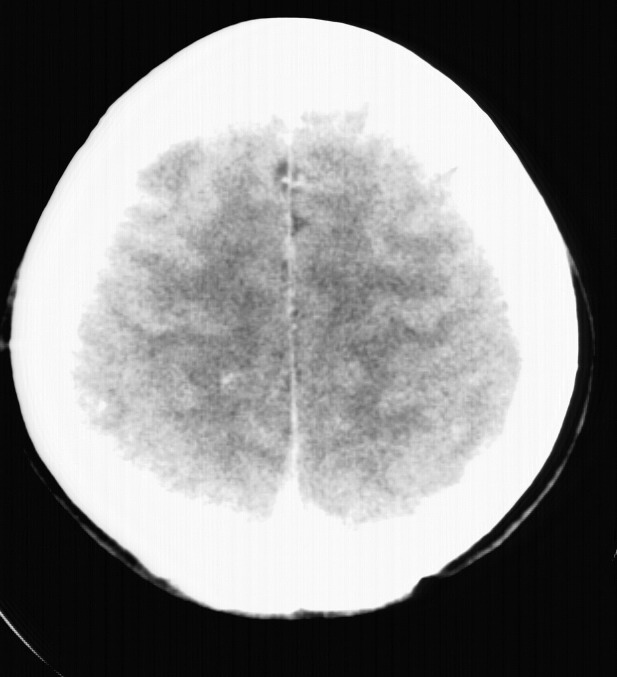

标题: CT5853:右额叶上部占位请会诊

女,34岁,自述头晕胀2年,近期感精神恍惚,无发热,实验室检查阴性。

右顶叶靠近脑表面圆形低密度灶,周围无水肿及占位效应,增强病灶无明显强化,考虑:右顶叶低分级星型细胞瘤。

右额叶上部皮质区见类圆形低密度区,边界不清,无强化,无钙化。

支持大多数战友的意见,1级星形细胞瘤。